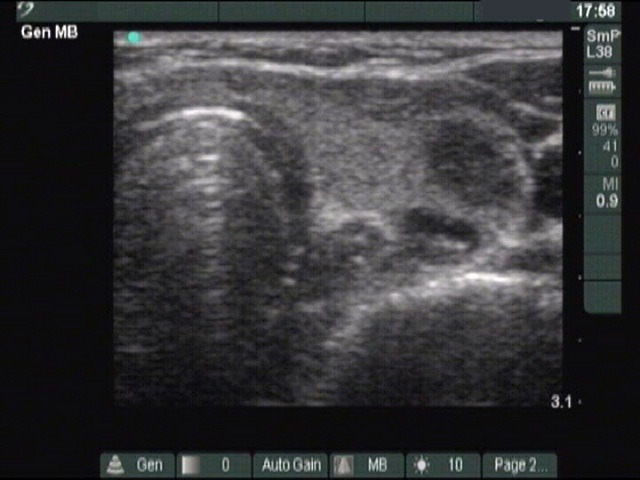

Ultrasonography: There were three hypoechogenic lesions wich has hyperechogenic granules larger than foci of microcalcification. There was a lymph node above the left lobe. The node lacked a regular hilum and was round

Comment. The coarse and large hyperechogenic figures seen on ultrasonography correspond to amyloid deposits. In contrast with coarse calcification, there is no acoustic shadow dorsal to amyloid. The foci of amyloid are much larger than a microcalcification. The specificity of this type of hyperechogenic figures is around 50%.